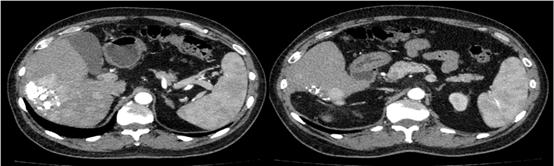

基于mRECIST标准,可判定为一线治疗后疾病进展。遂换用瑞戈非尼联合PD-1单抗治疗。2020年7月6日异常凝血酶原降至49.89 ng/ml。2020年9月17日再次复查,肝增强CT提示,肝脏多发占位性病变,病灶内可见肿瘤存活。病情较前稳定,未见显著进展。

图片

图:肝增强CT(2020-9-17)